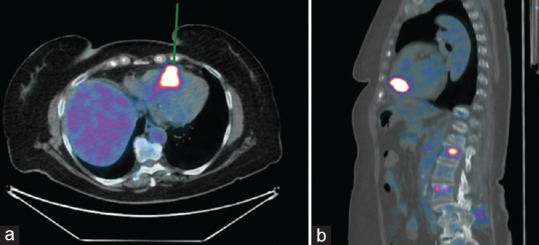

Heart metastatic tumors are more frequent than primary heart tumors. Cardiac metastasis is a rare phenomenon, occurring mainly by direct spread, especially from lung cancer. Cardiac metastases may be asymptomatic or cause arrhythmias, nonspecific electrocardiographic alterations, or mimic a myocardial infarction. In this case report, we illustrate a rare case of pulmonary adenocarcinoma, which through the bloodstream developed a stalactite-shaped metastasis within the right ventricle of conspicuous size (20 mm × 34 mm × 12 mm). In addition, the tumor compressed the right pulmonary trunk, causing pulmonary hypertension. It is essential to characterize metastasis with multimodality imaging. Such lesions within the right cavities can cause massive pulmonary embolism, as in our case, leading to the patient's death, thrombolytic therapy not being effective.